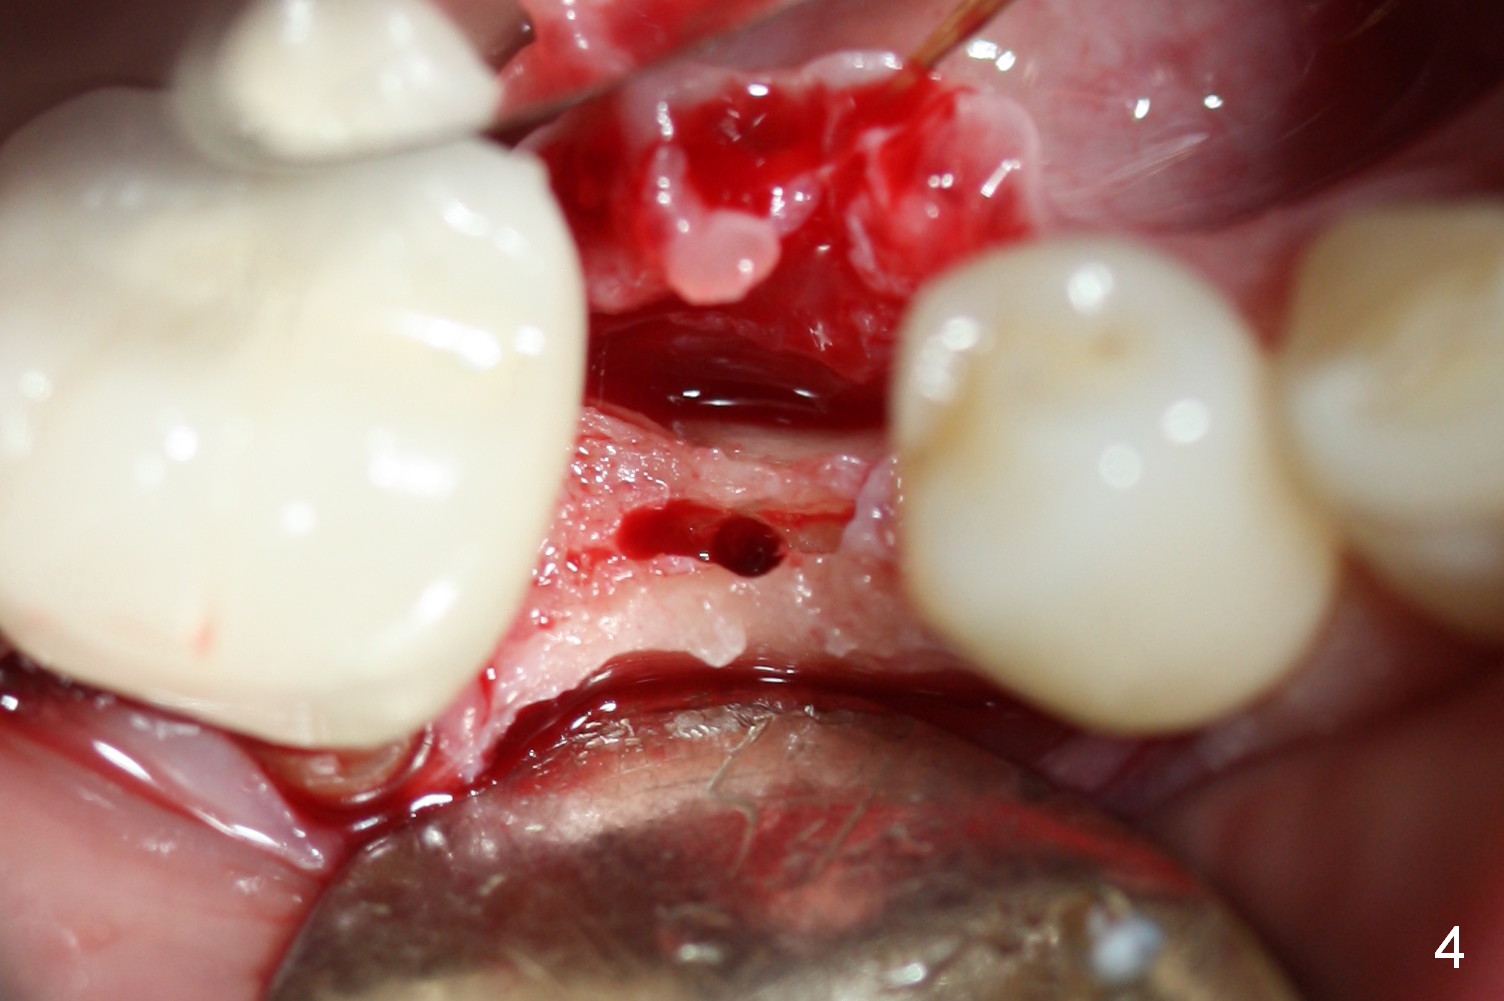

Preop photo shows the distal inclination of the tooth #28 (Fig.1). The distal surface of the latter is reduced before incision for implant placement at #29 (Fig.2). The buccolingual width is approximately 4 mm, as compared to 3 mm implant positioner (Fig.3). After 1.2x10 mm osteotomy (Fig.5), the mesiodistal cortical bone is removed with a small high-speed fissural bur (Fig.4). When a 2.5x12(2) mm 1-piece implant is placed (Fig.6), there is no buccal (Fig.7) or lingual plate perforation. There is no postop paresthesia. There is mild bone loss distal 4 months postop (Fig.8 *). Take photos before and after permanent crown cementation to show increase in ridge width after bone graft and improvement in gingival health after provisional modification. Take PA and/or BW post cementation to show that the distal bone resorption (Fig.8 *) is partially due to angulation. No continuous bone loss 15 months post cementation (Fig.9). There is mild bone resorption mesially 2 years 3 months post cementation (Fig.10). The soft and hard tissues remain healthy 4 years 3 months post cementation (Fig.11,12).